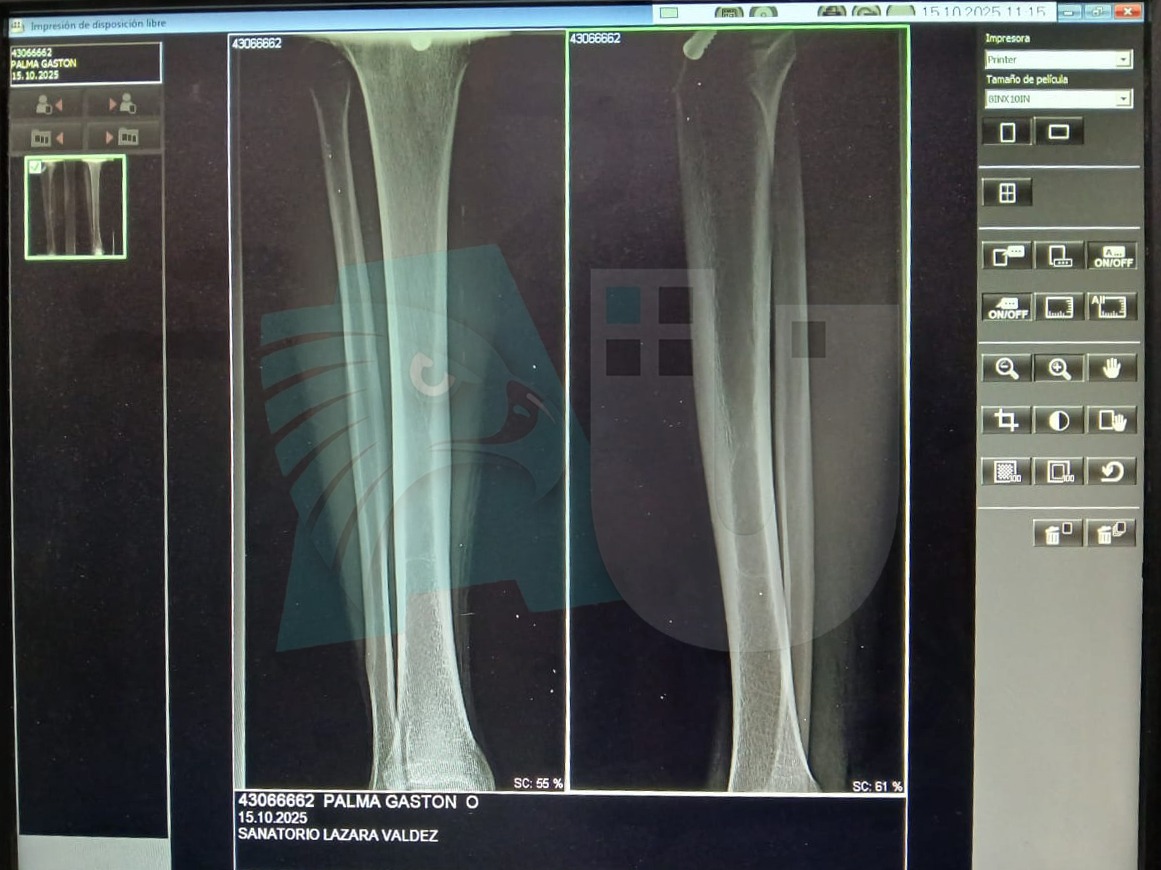

Según consta en el parte médico, el Cabo Palma presenta una herida de aproximadamente 3 centímetros con tres puntos de sutura en la cara anterior de la pierna derecha. El equipo de Medicina Legal Interior constató un tiempo de evolución superior a las 12 horas, estimando una curación total en menos de 30 días, siempre que no existan complicaciones.

Un dato tranquilizador es que el propio Cabo Palma informó a las autoridades que la radiografía realizada descartó que la parte ósea de su pierna se encuentre afectada. Luego de realizarse el control de signos vitales y la curación de la herida, se determinó que el empleado policial se halla en buenas condiciones de salud, siguiendo indicaciones de su médico particular de tomar antibiótico y analgésico.